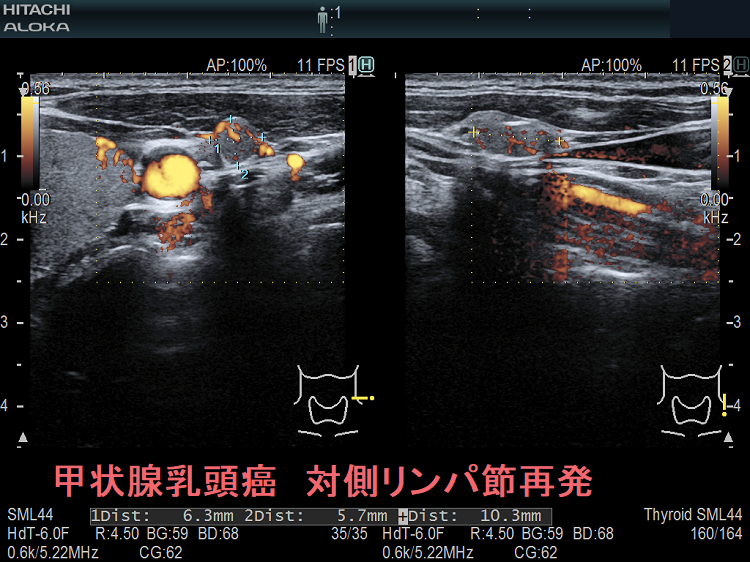

甲状腺乳頭癌の同側(切除した側)と対側(切除していない側)のリンパ節再発を同時に認めた症例

次の写真は甲状腺半葉切除(右葉)切除後リンパ節再発です。左右とも総頚動脈外側のリンパ節再発です。

甲状腺乳頭癌 対側(切除していない側)リンパ節再発 超音波(エコー)画像

甲状腺乳頭癌 対側(切除していない側)リンパ節再発 超音波(エコー)画像;等エコー、いびつな形で、周囲との境界が一部不明瞭化して浸潤を疑われる。リンパ門は消失。

甲状腺乳頭癌 対側(切除していない側)リンパ節再発 超音波(エコー)画像 ドプラーモード

甲状腺乳頭癌 対側(切除していない側)リンパ節再発 超音波(エコー)画像  ドプラーモード;内部に異常な走行の血管を認め、血流豊富。